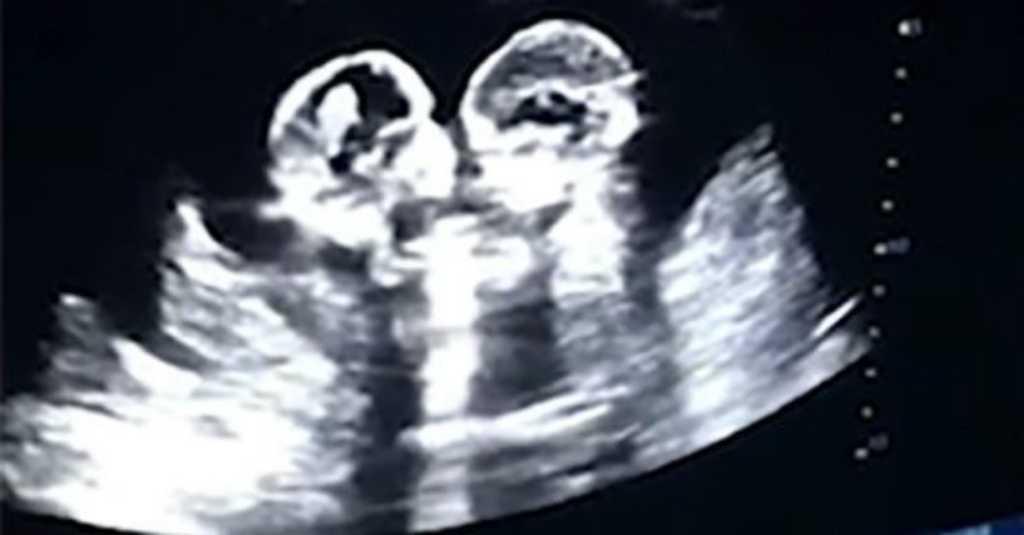

Pantau.com - Bayi kembar bertengkar memang sering terjadi, tapi bagaimana jadinya keduanya bertengkar saat masih berada di dalam kandungan ibunya. Seperti yang terjadi di China dimana dalam rekaman USG terlihat kedua bayi saling mendorong satu sama lain.

Diwartakan laman Metro, video ini direkam saat sang ibu tengah hamil empat bulan dan memeriksakan diri ke dokter.

Bayi kembar dalam kandungan terlihat sedang bertengkar. (Foto: China Daily/Miaopai)

Tao tak menyangka kedua putrinya menjadi perbincangan hangat di sosial media. Pada awal Januari lalu suami istri itu kembali memeriksakan kandungan, namun posisi kedua anaknya kali ini saling memeluk.